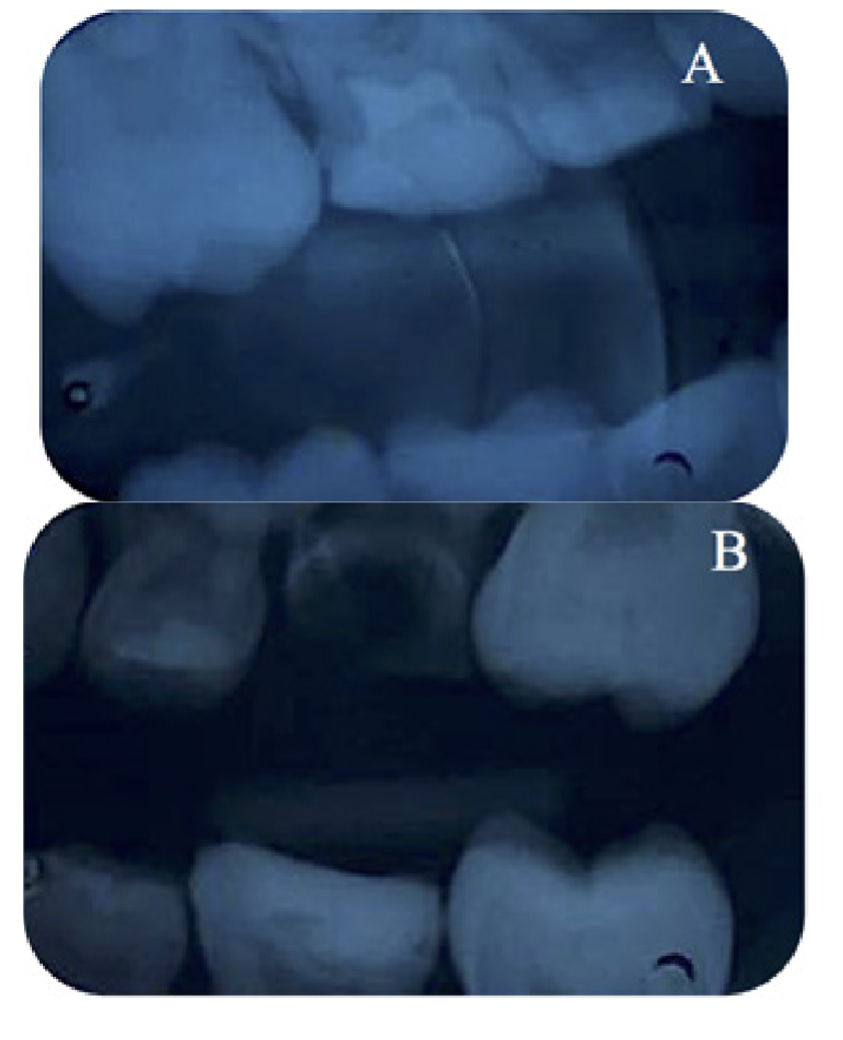

Figura 3. Control radiográfico después de 6 meses. A) Radiografía interproximal del diente 16; B) Radiografía interproximal del diente 26.

Después de 6 meses, el paciente volvió a observar y controlar los dientes sellados, y fue evaluado clínica y radiográficamente. Se observó una falla en la integridad del sellador en el diente 16 sin progresión de la lesión por caries. Como era un paciente que ya tenía antecedentes de lesión por caries, se decidió realizar una reparación siguiendo el procedimiento clínico descrito anteriormente, utilizando el mismo sellador de resina. El sellador del diente 26 estaba intacto (Figura 3).